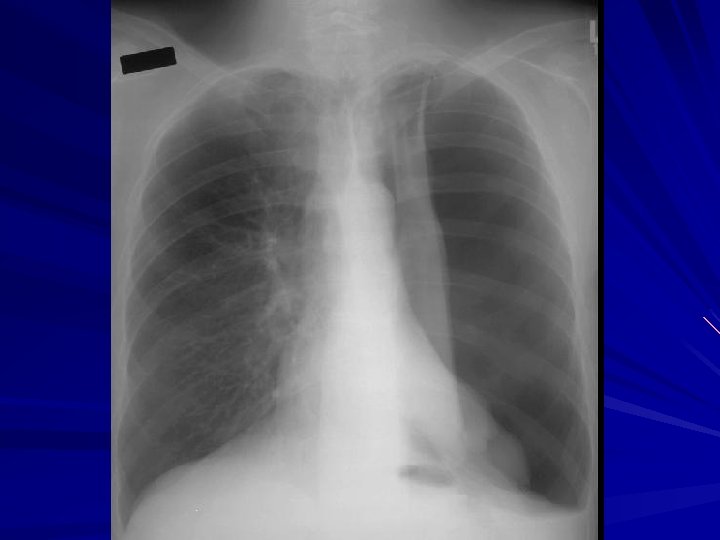

Pulmonary Edema Physical Examination: - Gallop Rhythm - ↑JVP - Basal Crackles - Lower Limb Edema Investigations: - CXR, ECG, ECHO Treatment : - Oxygen - Diuretics - Digoxin - After load Reduction